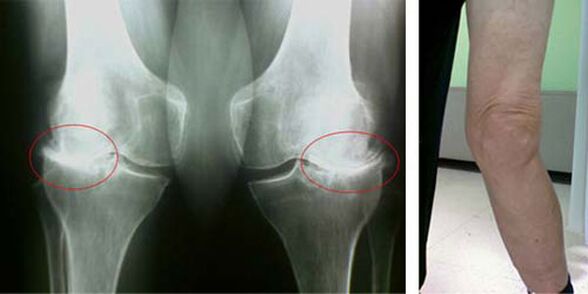

Početne faze pojave takve patologije kao što je artroza zgloba koljena ne vizualno se očituju ni na koji način. No, nakon određenog vremena pacijent uočava znakove deformacije koljena, kao i karakterističnu zakrivljenost duž osi potkoljenice (usmjerena prema unutra). Postoji i krckanje kada treba savijati nogu.

Prisutnost boli, ograničeno kretanje u koljenu čini osobu da posjeti liječnika i podvrgne se pregledu. Da bi to učinio, mora proći testove i napraviti rendgenski snimak bolesnog zgloba. Ako ove mjere nisu dovoljne za potvrdu artroze zgloba koljena, tada se radi magnetska rezonancija. Na temelju prikupljenih podataka liječnik odabire najbolje metode liječenja.